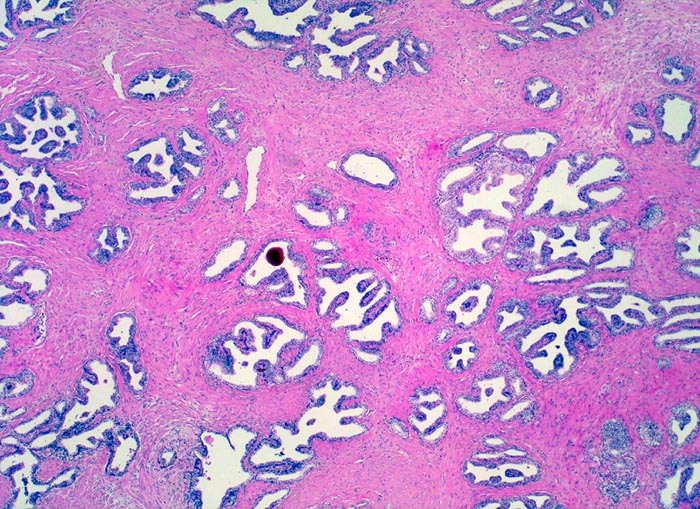

• Normale Prostatadrüsen mit grossen Lumina angeordnet in Läppchen. Das Epithel bildet Falten und besteht aus einer inneren hochprismatischen sekretorischen Zellschicht und einer äusseren Schicht flacher Myoepithelien.

• Herde kleiner Karzinomdrüsen ohne Basalzellschicht.

• Fehlende lobuläre Anordnung der Karzinomdrüsen.

• Konfluierende Drüsen bilden kribriforme Muster.